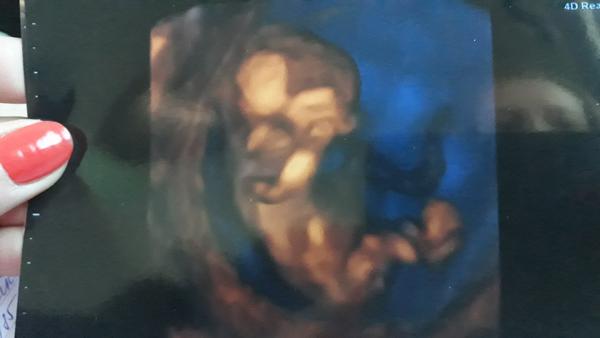

Holky já jsem včera byla na kontrole - měla bych být 11+2, a mimčo odpovídalo 10+6, takže jak to vypadalo že je o týden mladší podle minulých dvou UTZ tak už ten rozdíl je menší, všechno je prý vpořádku a v jednu chvíli bylo vidět jak se krásně protahuje - ty malinké prstíčky 🙂 Fotka je jakože hlavou dolů a ručičky má na hrudníčku - ale není to moc ostré - přijde mi že na tom monitoru to bylo vidět čistěji - byl vidět i nosík a očička hezky